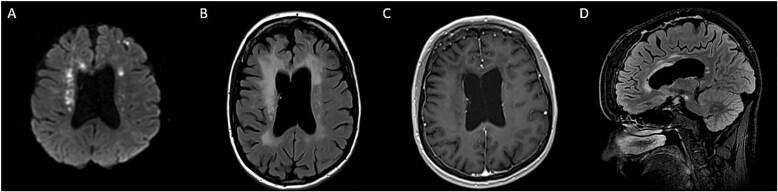

A 43-year-old female with personality changes and alien limb.

Colony stimulating factor-1 receptor encodes for a tyrosine kinase receptor expressed on microglia. related disorder is a devastating autosomal dominant leukoencephalopathy caused by with variable penetrance in adults. It remains significantly underdiagnosed or misdiagnosed. We report a case of a 43-year-old woman with an insidious onset of neurocognitive decline, alien limb phenomenon, and personality changes over 1 year. In this report we will discuss the clinical approach, differential diagnosis, investigation, and available treatment options for related disorder.